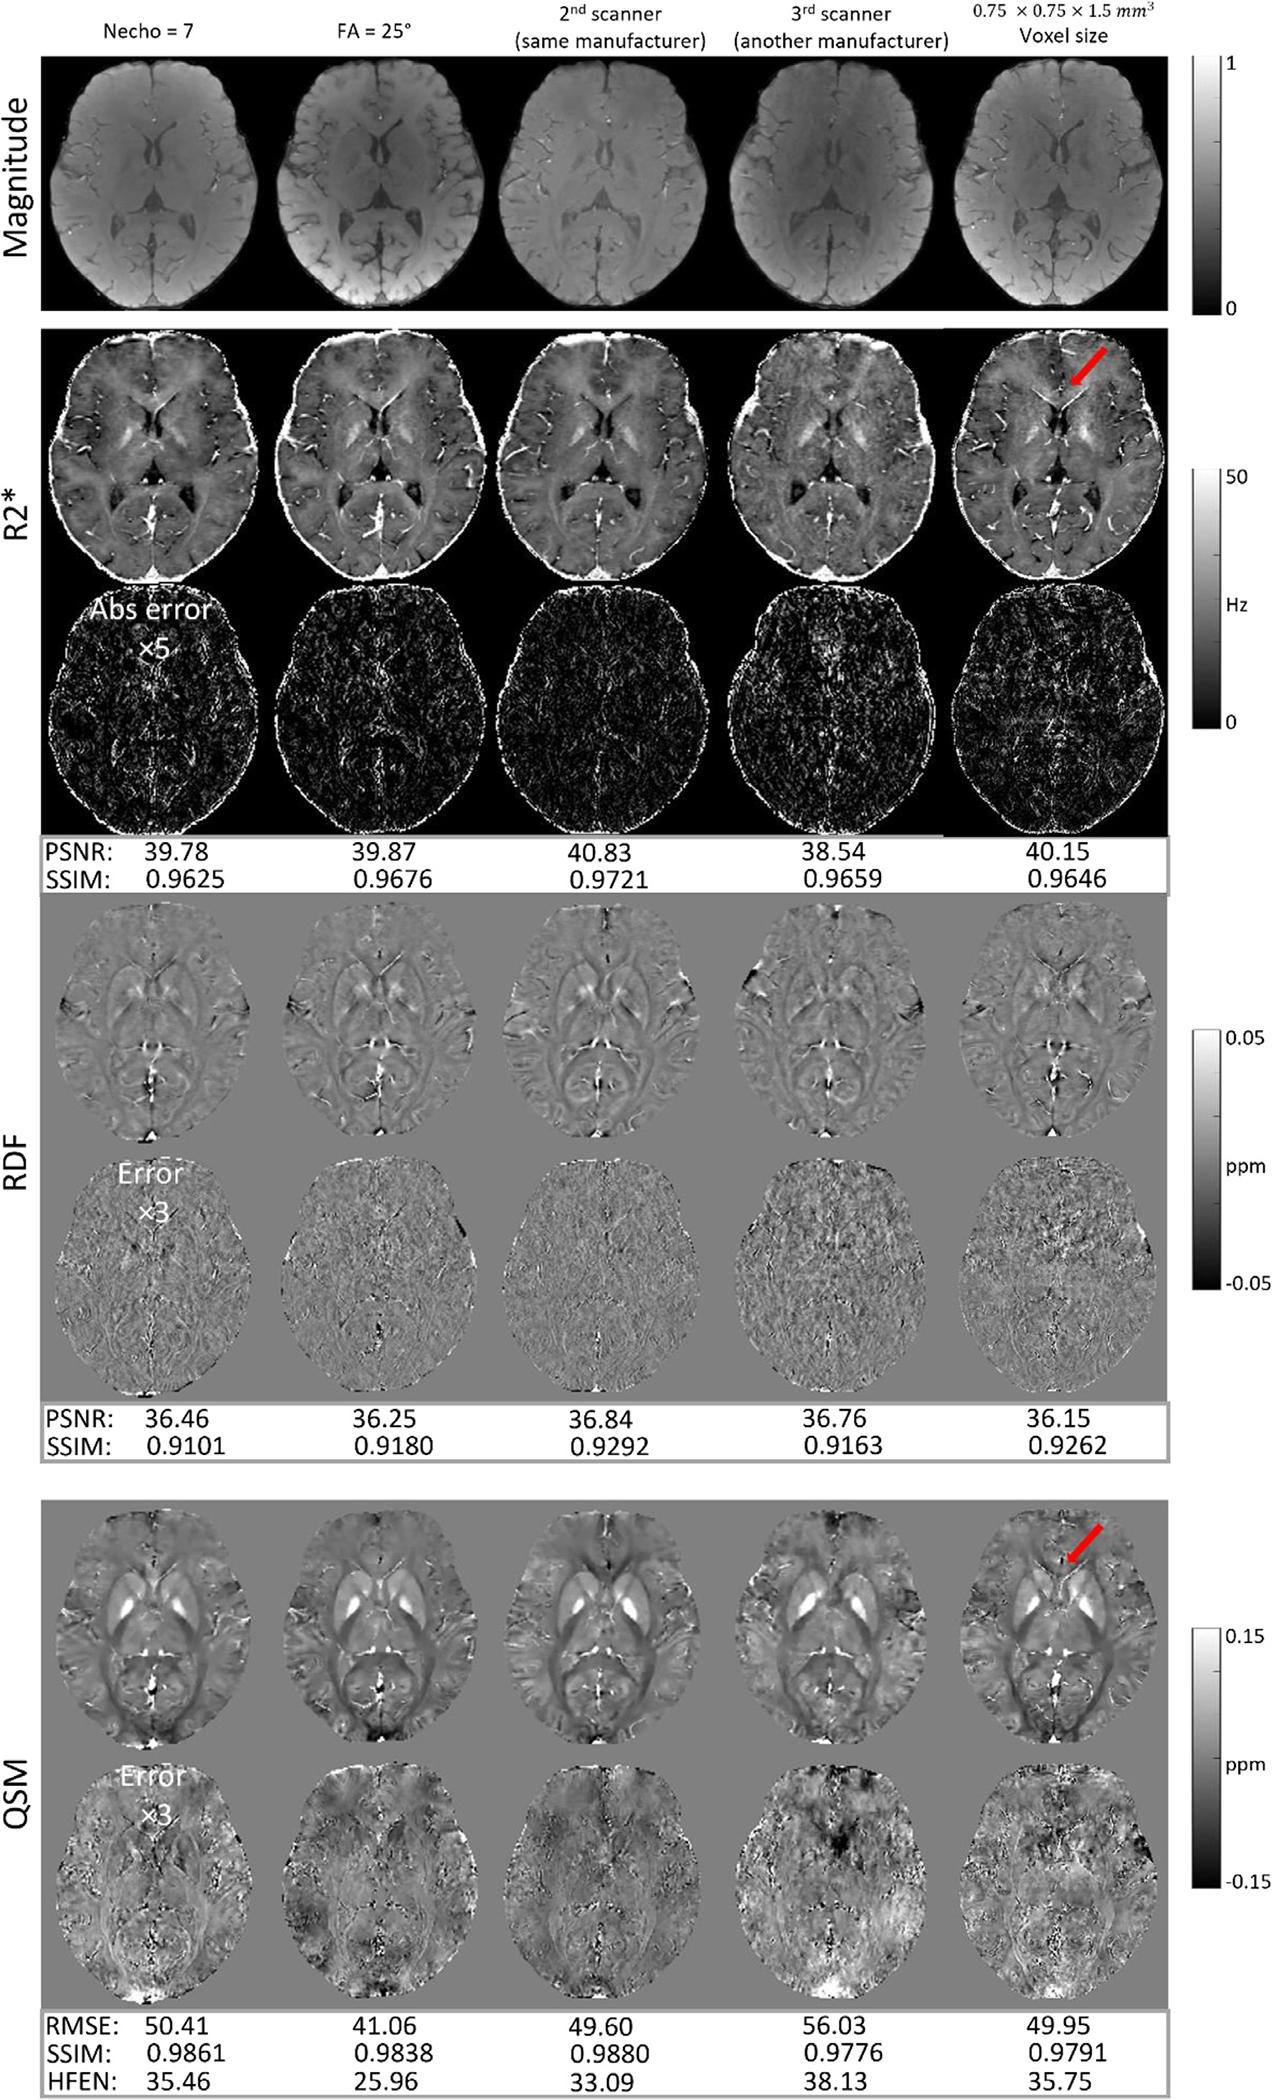

Quantitative susceptibility mapping (QSM) involves acquisition and reconstruction of a series of images at multi-echo time points to estimate tissue field, which prolongs scan time and requires specific reconstruction technique. In this paper, we present our new framework, called Learned Acquisition and Reconstruction Optimization (LARO), which aims to accelerate the multi-echo gradient echo (mGRE) pulse sequence for QSM. Our approach involves optimizing a Cartesian multi-echo k-space sampling pattern with a deep reconstruction network. Next, this optimized sampling pattern was implemented in an mGRE sequence using Cartesian fan-beam k-space segmenting and ordering for prospective scans. Furthermore, we propose to insert a recurrent temporal feature fusion module into the reconstruction network to capture signal redundancies along echo time. Our ablation studies show that both the optimized sampling pattern and proposed reconstruction strategy help improve the quality of the multi-echo image reconstructions. Generalization experiments show that LARO is robust on the test data with new pathologies and different sequence parameters. Our code is available at https://github.com/Jinwei1209/LARO-QSM.git.

定量磁化率映射(QSM)涉及在多个回波时间点采集和重建一系列图像,以估计组织场,这延长了扫描时间,并需要特定的重建技术。在本文中,我们提出了一个新的框架,称为学习采集和重建优化(LARO),旨在加速用于 QSM 的多回波梯度回波(mGRE)脉冲序列。我们的方法涉及使用深度重建网络优化笛卡尔多回波 k 空间采样模式。接下来,使用笛卡尔扇形束 k 空间分段和排序,在前瞻性扫描中在 mGRE 序列中实现此优化的采样模式。此外,我们建议在重建网络中插入一个递归时间特征融合模块,以捕获沿回波时间的信号冗余。我们的消融研究表明,优化的采样模式和提出的重建策略都有助于提高多回波图像重建的质量。泛化实验表明,LARO 在具有新病理学和不同序列参数的测试数据上具有稳健性。我们的代码可在 https://github.com/Jinwei1209/LARO-QSM.git 上获得。